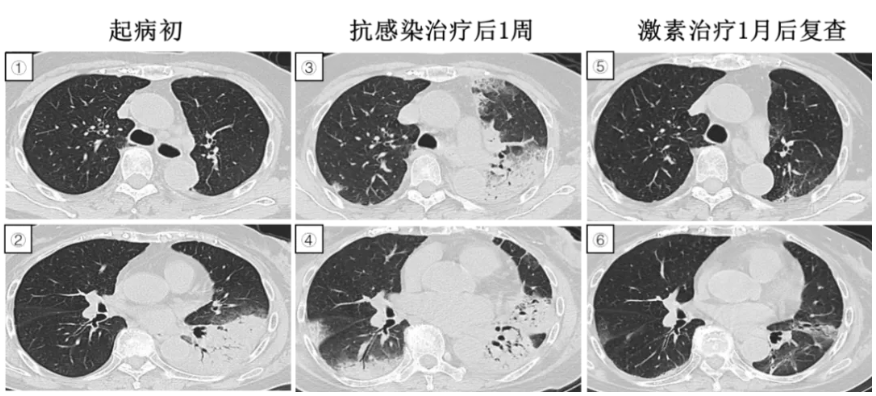

图2:①-②入院时CT提示散在分布纤维条索影。③-④入院后4天复查CT提示双肺透亮度降低,弥漫性单薄磨玻璃样改变,双下肺地图状实变影。⑤-⑥CT提示肺纤维化改变。

入院第3天,稍活动即感气促明显,不吸氧SpO2 90%。入院第6天呼吸困难,SpO2 96%(储氧面罩10L/分)。入院第12天呼吸困难加重SpO2 77-87% (储氧面罩10L/分),。住院期间胸部CT提示双肺炎症渗出,逐渐间质纤维化改变。尿百草枯浓度检测 0.9 µl/ml。

疾病要点:百草枯中毒由超氧自由基通过脂质过氧化作用损伤人体细胞,最常受累的器官主要是肺、肾和肝脏,在肺实质中浓度可高达血浆浓度的十倍以上。临床表现取决于摄入量,由于目前尚无特效解毒剂,支持性治疗是百草枯中毒治疗的主要手段。高分辨率CT早期异常表现为双肺弥漫性磨玻璃样密度影,随后发展为伴有牵拉性支气管扩张的实变,晚期表现为肺纤维化形成,大多数百草枯引起的肺纤维化累及肺的中央区域。